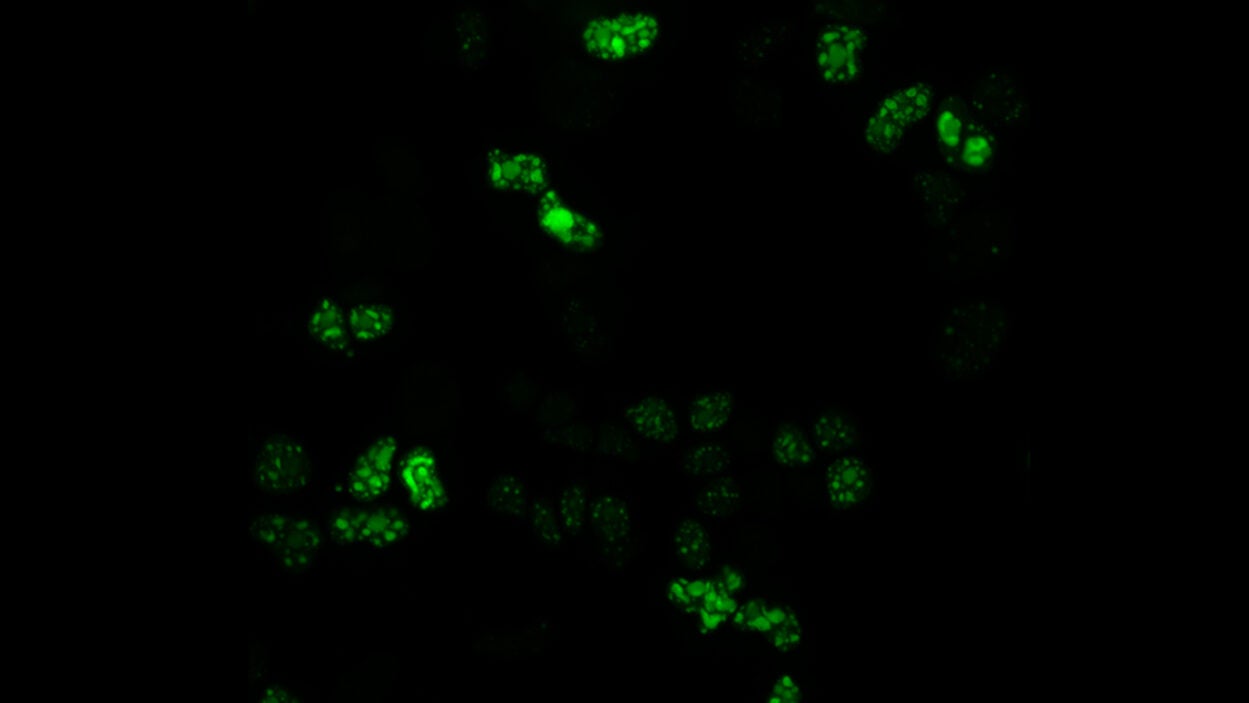

Speckles sound innocent enough, like little spots. But don’t be fooled. These tiny structures could someday have big implications for cancer care. Listen to the podcast »

What are nuclear speckles and how might these mysterious structures impact your DNA? Get an inside look from CSHL Assistant Professor Kate Alexander. Watch the video »

Research from new CSHL Assistant Professor Katherine Alexander suggests that nuclear speckles could influence kidney cancer patient outcomes. Read the story »

Stunning new images from CSHL’s Joshua-Tor lab reveal how the protein complex interacts with differently shaped primary microRNAs. Read the story »

Her team will explore mysterious cellular structures known as nuclear speckles and their role in diseases such as cancer. Read the story »